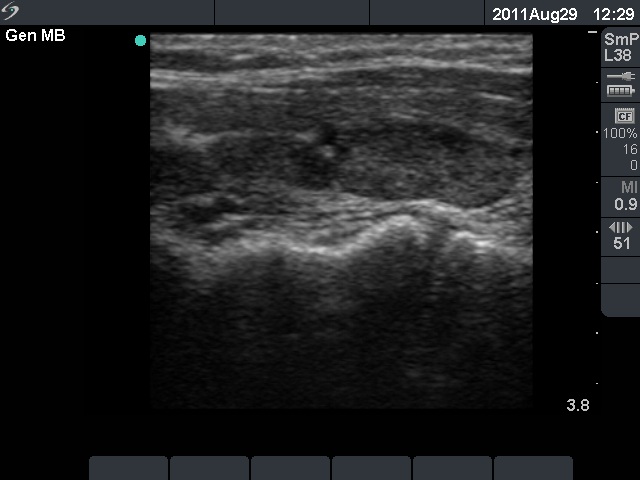

First examination (first row of images):

Clinical presentation: A 50-year-old woman was referred for evaluation of complaints suggesting hypothyroidism.

Palpation: Both lobes were firm.

Laboratory tests: TSH 23.7 mIU/L. Other results including serum calcium and phosphorus were in the normal range.

Ultrasonography: The thyroid was moderately hypoechogenic. There were two more hypoechogenic lesions in the dorsal part of the right lobe.

Aspiration cytology of the lesions in the dorsal part of the thyroid resulted in Hashimoto's thyroiditis.

Daily 75 microgram levothyroxine was given. We advised beside checking the TSH level, a follow-up ultrasound examination 2 years later.